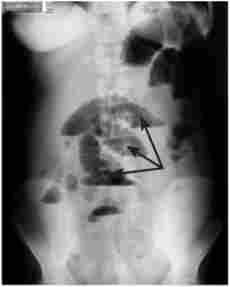

Для уточнення діагнозу застосовуються інструментальні методи дослідження. Всім хворим з підозрою на гостру кишкову непрохідність виконується оглядова рентгенограма живота. Знімок робиться у вертикальному положенні хворого в прямій проекції. Якщо через важкість стану хворий не може стояти на ногах, дослідження виконують в латеропозіції (горизонтальне положення на боці). У сидячому положенні досліджувати хворого не варто, так як при цьому на знімку видно лише верхня половина живота. Наявність на рентгенограмі горизонтальних рівнів рідини зі скупченням внутрикишечного газу над ними (чаш Клойбера) - основний рентгенологічний ознака ОКС (рис. 23.4).

Оглядова рентгенограма живота

Мал. 23.4. Оглядова рентгенограма живота.

Чаші Клойбера (вказані стрілками)